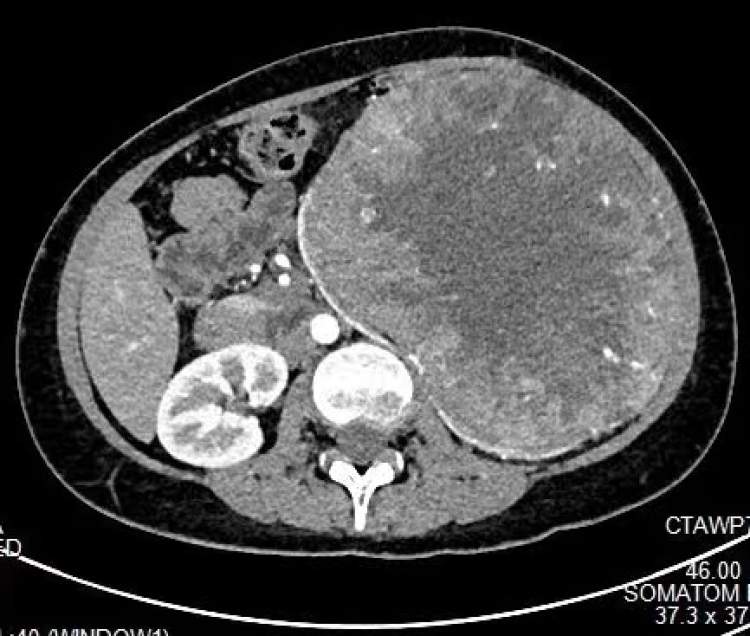

这位病人近几月发觉腹部逐渐膨隆,原以为是身体发胖引起,到医院检查才发现左肾内有罕见巨大肿瘤,腹部如同藏着一个如同40码鞋子大小的“炸弹”,肿瘤已达盆腔,严重挤压胃肠道等腹腔脏器,随时可能破裂引发大出血。上海交通大学医学院附属新华医院泌尿外科主任崔心刚教授带领的肾肿瘤团队顺利完成高难度肾肿瘤切除术,“拆弹保肾”,有惊无险。

小吴入院后快速完成了影像学检查和全身情况的评估。专家团队为小吴进行了智能三维建模,明确了肿瘤与肾脏动静脉及周围脏器的关系。完善术前评估后,崔心刚邀请并组织了多学科会诊,共同讨论制定手术方案及风险处理预案,拟定在充分备血和肾动脉介入栓塞后,进行传统开放手术切除肾肿瘤。